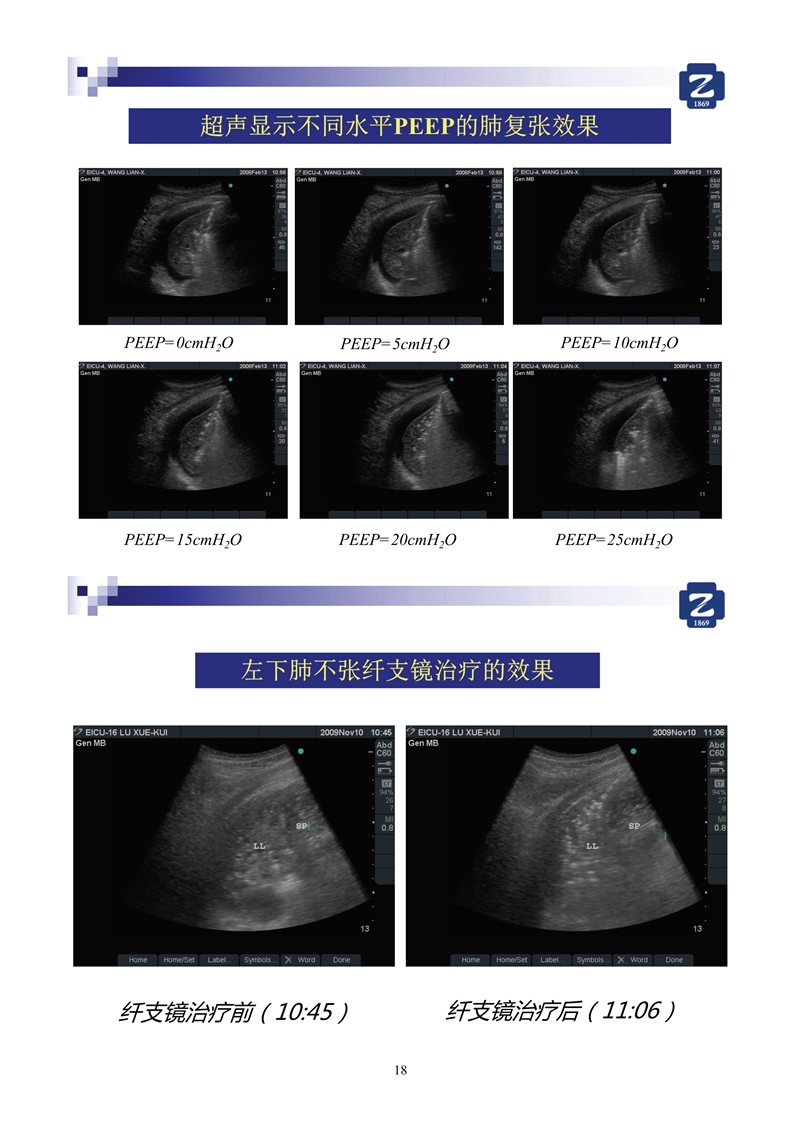

第二版新型冠狀病毒肺炎超聲診斷實(shí)用手冊_2.jpg

第二版新型冠狀病毒肺炎超聲診斷實(shí)用手冊_64.jpg